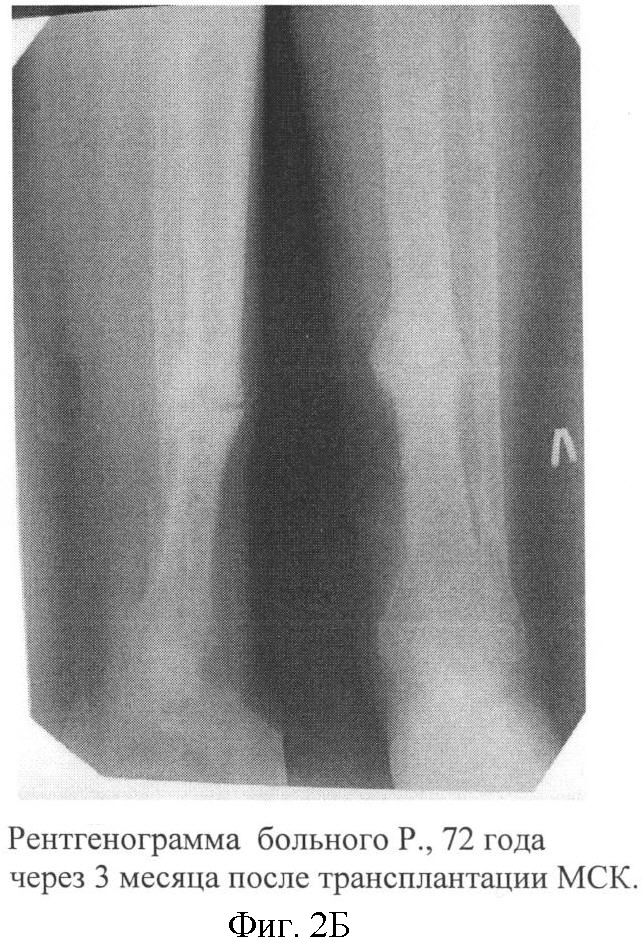

Больной Р., 72 года, поступил в хирургическом отделении МУЗГКБ 2 с диагнозом: «Хронический посттравматический остеомиелит левой большеберцовой кости в средней трети, свищевая форма; патологический перелом с признаками ложного сустава в средней трети левой большеберцовой кости, в условиях ОМС (пластина с шурупами)». Травма 2.5 года назад – закрытый перелом костей левой голени в нижней трети. После накостного остеосинтеза развился остеомиелит. Проводимые лечебные мероприятия привели к консолидации перелома в нижней трети, но у больного сохранялся свищ с гнойным отделяемым и остеомиелитический процесс перешел в среднюю треть большеберцовой кости, где на уровне проксимального шурупа произошел патологический перелом (фиг.2А). Больной передвигался с помощью костылей без опоры на больную конечность. 24.02.08 г. выполнена операция – иссечение свища, удаление металлоконструкции, некрсеквестрэктомия, дренирование остеомиелитического очага. Иммобилизация гипсовой повязкой. Купировав острый воспалительный процесс, выполнены трансплантации МНК и МСК по описанной схеме. Отмечено заживление послеоперационной раны первичным натяжением, без признаков рецидива воспалительного процесса за период наблюдения. Через 3 месяца после имплантации: клинически перелом консолидировал, гипсовая повязка заменена на съемную гильзу. На контрольной рентгенограмме отмечается выраженная костная мозоль в области перелома средней трети большеберцовой кости. Периостальная реакция не отмечается (фиг.2Б). Больной ходит, используя трость с опорой на пораженную конечность. Данная картина сохраняется через 6 месяцев.